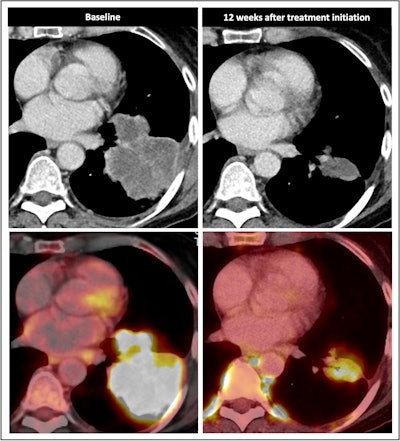

Radiological response inconsistent with pathological response: 75-year-old patient received a neoadjuvant treatment with three cycles of ICIT + C (carboplatin/pemetrexed/pembrolizumab). 12 weeks after treatment began, the patient showed complete pathologic response (ypTo, pNo) but only partial radiological response.

An important limitation of F-18 FDG-PET/CT is its restricted ability to identify patients with cPR, according to the researchers. Also, patients with partial metabolic response can have either cPR, MPR, or non-MPR, and the technique fails to distinguish between true nodal progression and the so-called nodal immune flare/sarcoid-like reaction. Additionally, RECIST 1.1 and iRESCIST 1.1 are of limited value as they are neither designed nor validated to be applied in the setting of neo-adjuvant ICIT+C, they concluded.